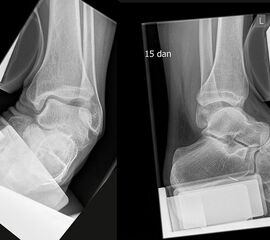

Massive Schwellung und Hämatomverfärbung 2 Tage nach 2-Band-Verletzung.

Die klinischen Beschwerden nach dem Distorsionstrauma liefern wichtige Anhaltspunkte für die Schwere der Verletzung. Kann nach einem Distorsionstrauma der Fuß voll belastet werden, ist eine knöcherne unwahrscheinlich 15. Bei einer Verletzung des lateralen Kapsel-Band-Apparats finden sich Schwellung, Hämatom (Abb. 2) sowie - je nach Ausmaß der Instabilität - ein positiver Talusvorschub und eine laterale Aufklappbarkeit 16.